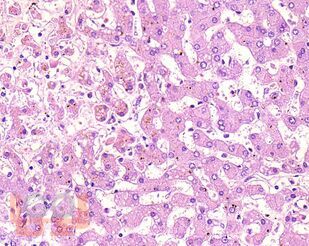

В учебном пособии представлен теоретический материал, перечень макропрепаратов и микропрепаратов, демонстрирующих типовые проявления патологических процессов. В цветных иллюстрациях и в описании микропрепаратов

сделан акцент на наиболее важных гистологических изменениях, позволяющих на светооптическом уровне диагностировать и дифференцировать состояния, отклоняющиеся от нормы, в том числе с использованием различных гистологических окрасок. Пособие помогает выделить главные аспекты изучаемых патологических процессов, организовать и конкретизировать учебный процесс.